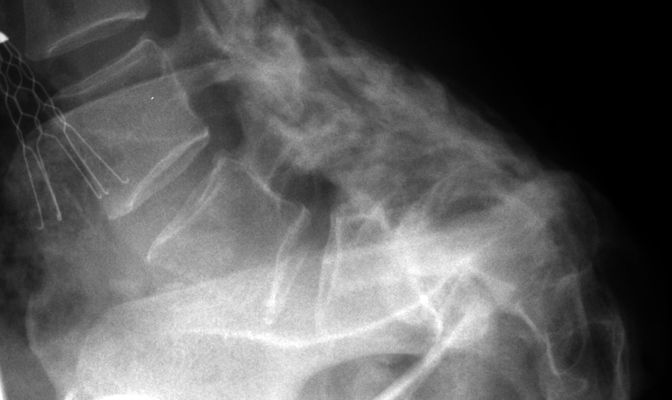

Frontal and lateral radiographs of the lumbar spine revealing anterolisthesis of the L5 vertebral body with the typical inverted Napoleon Hat sign. This sign is reserved for spondylolisthesis of the L5 vertebral body. With a case of spondylolisthesis, the AP radiograph will reveal the anterior border of the transverse process in continuity with the anterior border of the body of the same vertebrae. This continuous anterior border of the L5 vertebrae will be projected against the shadow of the sacrum, and appear as an upside-down (or inverted) Napoleon hat.

Lateral Lumbar Spine - Click on the image for a larger versionAAP L-S spine - Click on the image for a larger versionB